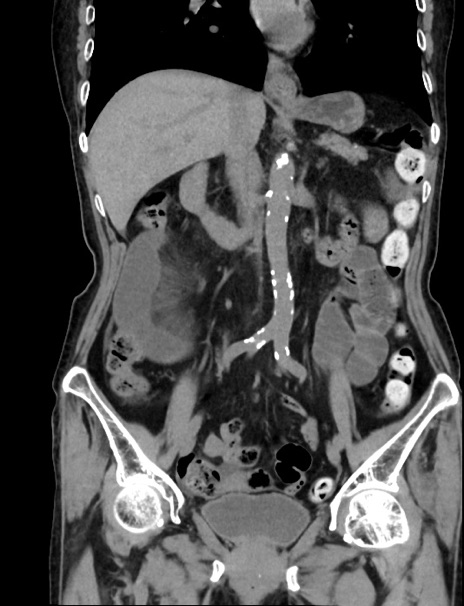

症例33(冠状断像)

【症例】70歳代 女性

【主訴】心窩部痛

【現病歴】延髄病変の精査・加療にて神経内科入院中。本日より心窩部痛あり。

【身体所見】右下腹部を中心に圧痛と反跳痛あり。